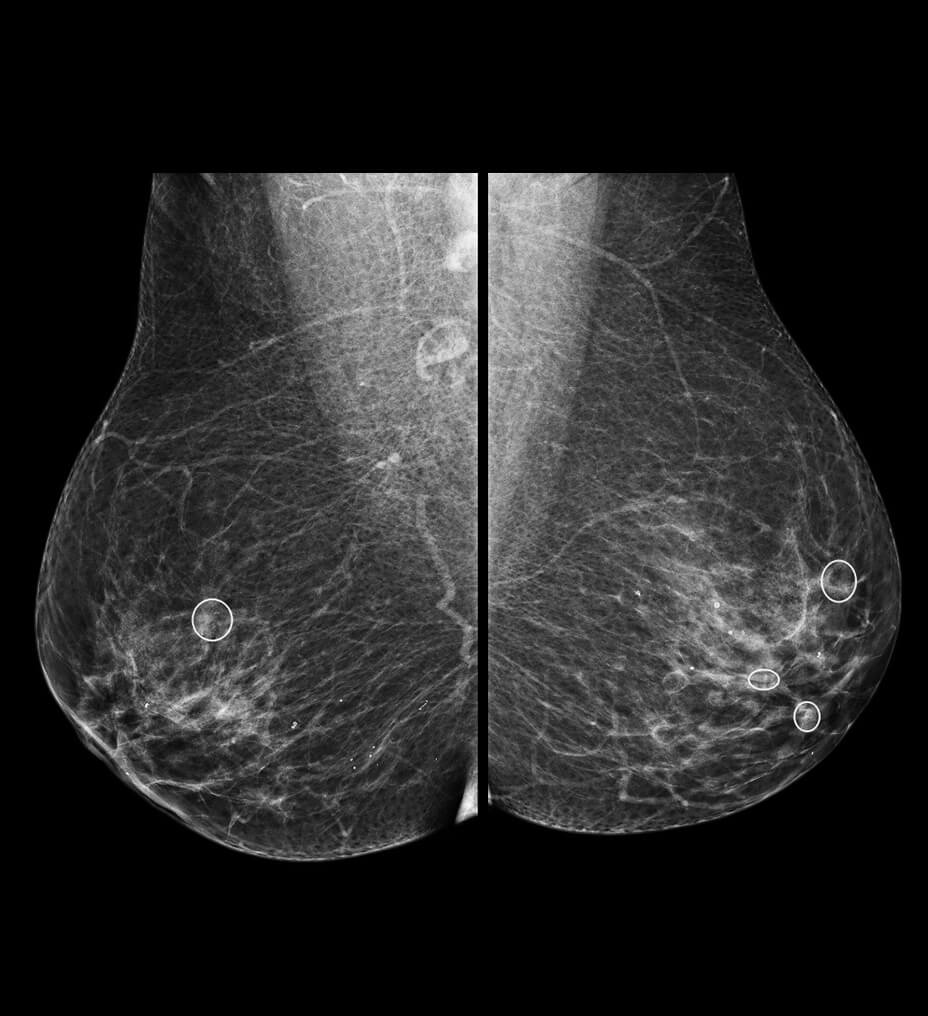

Follow nerve block procedures with cNerve

Helps detect and track nerves in 99% of cases during live scanning or while reviewing a stored clip2 while also displaying a distribution map of the areas on the body impacted by the selected nerve block procedure.